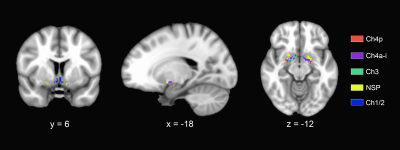

Significant differences in the volumes of the basal forebrain and the right hippocampus were observed among the four groups. More specifically, the B-SCD and MCI groups showed decreased volumes in the basal forebrain than the NC and G-SCD groups. The MCI group showed significantly atrophied right hippocampus than the other three groups. Subfield analyses of the basal forebrain and the right hippocampus suggested that the B-SCD group showed decreased volumes in the Ch4p and Ch4a-i subregions than the NC and G-SCD groups, and the MCI group showed decreased volumes in all the subregions of the basal forebrain. As for the right hippocampus, the MCI group showed atrophied subregions of the subiculum, CA1, presubiculum, molecular layer, dentate gyrus, CA4, and HATA. Subfield volumes of the basal forebrain and the right hippocampus showed significant associations with cognitive measures. Greater volumes in the Ch4p were associated with greater language (r = 0.186, p = 0.014), executive (r = 0.271, p < 0.001), and navigation function (r = -0.180, p = 0.017). Greater volumes in the Ch4a-i were associated with great performance on the executive tests (r = 0.192, p = 0.011). Furthermore, structural covariance network of basal forebrain and right hippocampal subfields showed that the B-SCD group had a larger Lp and a larger lambda than the G-SCD group. Follow-up data revealed that the B-SCD group had a significantly higher conversion rate to MCI than the G-SCD group.

Figure 3. Segmentation of the basal forebrain subfields.